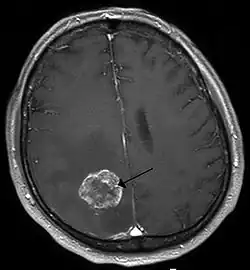

Brain - CT scan - Metastatic Pulmonary Adenocarcinoma. Arrow points to extensive edema of frontal lobe due to 23mm mass. Second area of edema can be seen in the left parietal-occipital region. - Genitourinary tract cancers, 11%

Brain imaging (neuroimaging such as CT or MRI) is needed to determine the presence of brain metastases.[6] In particular, contrast-enhanced MRI is the best method of diagnosing brain metastases, although primary detection may be done using CT.[10] Positron emission tomography (PET) is usually not considered suitable for imaging of brain metastases, because the most frequently used PET-radiotracer, 18F-FDG, does not only accumulate in the tumor but is naturally taken up by normal brain tissue, usually resulting in insufficient tumor-to-background contrast. PET-imaging of brain metastases is however feasible using alternative radiotracers, such as the Gallium-68 labeled peptide 68Ga-Trivehexin,[13] a tracer targeting the tumor cell surface protein αvβ6-integrin. 68Ga-Trivehexin demonstrated high uptake in a brain metastasis of tonsil carcinoma but no uptake in the surrounding healthy brain tissue, enabling a delineation of the brain metastasis (see image).[14]